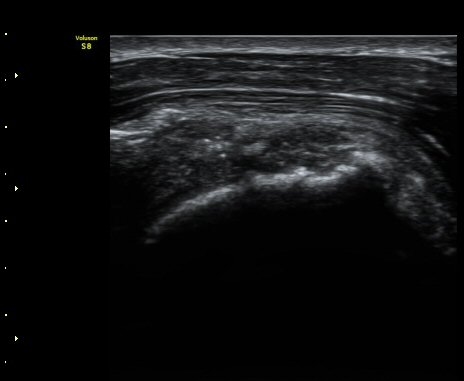

ÃÊÀ½ÆÄ °Ë»ç

ÀÌµÎ¹Ú±Ù°Ç È¾´Ü¸é°Ë»ç¿¡¼­ °ÇÁÖÀ§¿¡ ¼Ò·®ÀÇ ¼ö¾×Àú·ù¿Í Á¡¾×³¶³» ¾×Àú·ù°¡ °üÂûµÈ´Ù(»çÁø 1, 2).